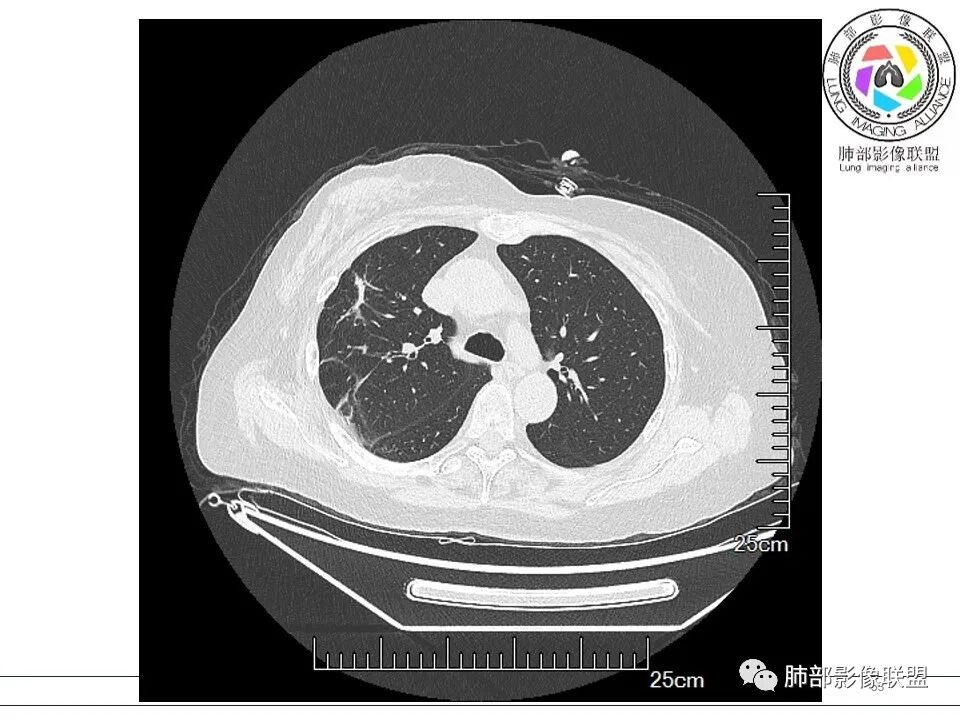

谢加平: 右肺上叶外周,近胸膜下结节病灶,侧向融合,边缘清,见平直边,与胸膜平行分布,支气管进入略扩张,周围见多发长索条影,方向肉芽肿性炎症,建议隐球菌荚膜抗原检查,肿瘤不支持,经皮肺穿刺病理检查!

宇宙: 右肺上叶胸膜下结节,多结节融合,长轴平行胸膜,边缘模糊,周围长索条,胸膜牵拉,近端支气管充气扩张,考虑隐球菌,鉴别OP

黄棘: 右肺上叶近胸膜下病灶,多个融合,边缘清,与胸膜平行分布,支气管进入后堵塞,周围见多发长索条影,考虑隐球菌

果哣.: 右肺上叶靠近胸膜结节影,平直为主,边缘清晰,支气管进入后截断,有扩张,考虑炎性隐球菌可能

放射线 (王秀仙): 右肺上叶胸膜下结节样影,边缘平直收缩,胸膜牵拉,支气管进入病灶并扩张,部分支气管进入后阻塞,长轴平行于胸膜,周围可见片状及条索状影,隐球?机化性肺炎?

良孑: 右肺胸膜下多发结节,长轴与胸膜平行,部分病灶有多结节融合,可见近端支气管充气征,有晕征及晕中软毛刺,长期口服激素病史,抗炎效果欠佳。病灶形态单一,无播散性树芽,结节内无支气管穿行,单侧发病,收缩力差,可排除TB,OP及淋巴瘤,综和考虑支持隐球菌